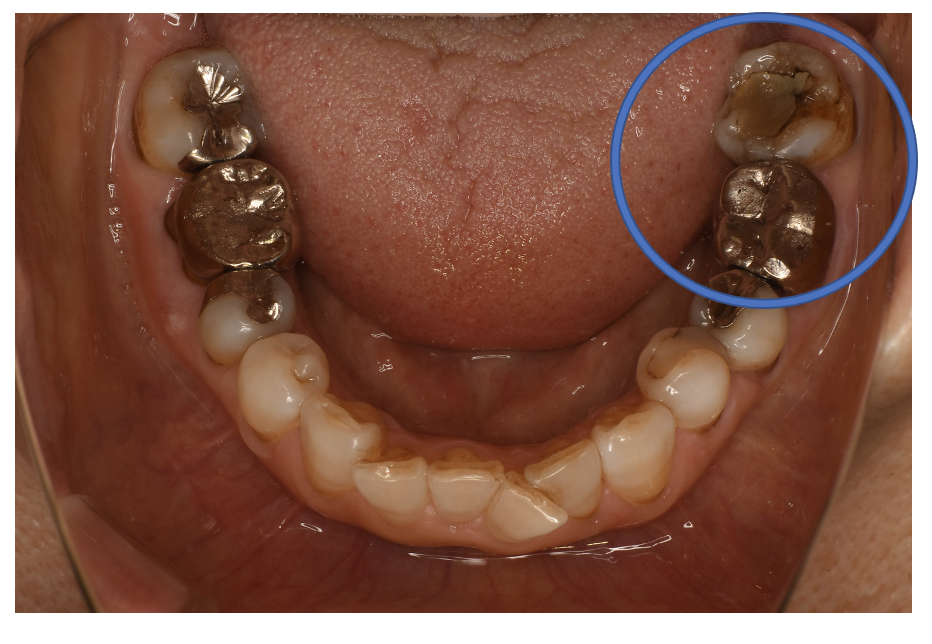

フルジルコニアCr 15 No.39

Before

| 治療方法 | フルジルコニアCr 虫歯などで失った歯質を天然歯と同じ色・質感のセラミックの一種であるジルコニア(人工ダイヤモンド)で補う治療法。 |

| 治療のデメリット | 変色がなく耐久性の高い治療ですが、歯周病や二次虫歯を予防するためには歯科医院での定期的なメインテナンスが大切です。 |

| 費用 | ¥89,000 |

| 通院回数 | 1ヶ月〜6ヶ月 |

| 備考 | 院長より プラスティック修復部の内部に虫歯が進行してしまっていたケースです。中を開けて見てみると、外から想像するよりもはるかに虫歯が 広がってしまっていました。幸運にも神経を保存できたので、生きた臓器としてまだ使うことが可能です。残存歯質がかなり薄く弱くなってしまったので、ジルコニアで被せて守ってあげています。 |